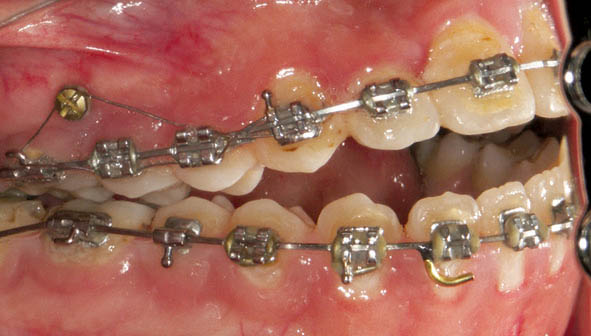

در بیمار اپن بایت (شکل 38-3 الی 40-3) در هر دو سمت چپ و راست یک مینی اسکرو در سمت باکال (شکل 41-3 الی 43-3) و یکی در سمت پالاتال (شکل 47-3) قرار میدهیم. آرچ وایری که میگذاریم را در ناحیه بین کانین و پرمولر اول قطع میکنیم تا دندانهای خلفی با قدامی روی یکدیگر اثری نداشته باشند. وقتی آرچوایر سه تکه باشد دندانهای سگمنت قدام و خلف جداگانه مرتب میشوند. چهار قطعه چین الاستیک از مینی اسکرو باکال به براکت دندانهای پرمولرها و مولرها میاندازیم. چون گردن مینی اسکروها برای چهار قطعه چین الاستیک کوچک است، لذا یک سیم لیگاچور از درون این چهار قطعه چین الاستیک رد میکنیم و آن سیم لیگاچور را به مینی اسکرو درگیر میکنیم تا یک نیروی اینترود کننده روی سمت باکال سگمنت خلفی اعمال شود. از سمت پالاتال هم چند باتن میچسبانیم و همین کار را در سمت پالاتال انجام میدهیم. البته در شکل 41-3 الی 43-3 دندانها در سمت باکال زیادتر از سمت پالاتال اینترود شدند، لذا سمت باکال با سیم لیگاچور به مینی اسکرو وصل شده تا در همان وضعیت بماند.

طی جلسات بعدی سمت پالاتال هم به اندازه باکال اینترود میشود تا نهایتاً درمان تمام گردد (شکل 44-3 الی 46-3).

شکل 41-3

شکل 42-3

شکل 43-3

شکل 41-3 الی 43-3: اینترود کردن سگمنت خلفی به کمک مینی اسکرو در سمت باکال منجر به اینترود بیشتر در سمت باکال و کمتر در سمت پالاتال میشود.